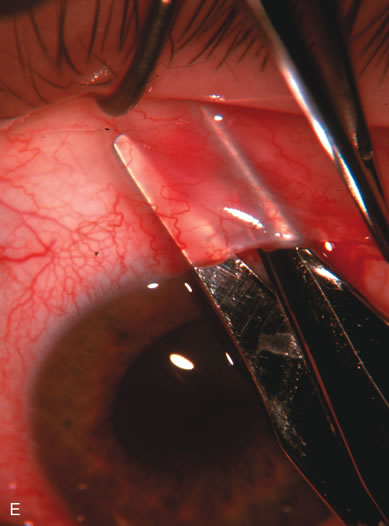

A patient with long-standing primary open-angle glaucoma with a successful glaucoma filtration procedure and IOP of 10 mm Hg on no antiglaucoma medications develops a significant, moderately dense nuclear sclerotic cataract. This patient is best served by small incision cataract extraction with foldable IOL implantation. Less desirable options include ECCE with IOL implant via clear cornea, temporal limbus, or inferior approach. Astigmatism, wound instability, prolonged visual recovery, visual fluctuation, exposed sutures, and bleb failure are the major drawbacks to large-incision lens extraction. Even after the surgeon has mastered large-incision clear corneal cataract extraction, long-term wound shift and astigmatism are a chronic problem (Fig. 6). Inferior cataract extraction is difficult for those not experienced with it. With the advent of small-incision phacoemulsification surgery, the surgeon is now able to use a limbus approach adjacent to the bleb or a clear corneal temporal approach. Postoperative inflammation is less with the smaller incision, and filtering blebs are more likely to survive. Patients with IOP greater than 10 mm Hg after a filtering procedure are more likely to experience permanent IOP elevation after phacoemulsification. Patients should understand that IOP elevation post cataract extraction is always an issue, even with a functioning filter.

Fig. 6. ECCE following trabeculectomy. The larger corneal incision associated with ECCE leads to a host of problems that are typically less severe with small incision cataract surgery. With improved phacoemulsification techniques, this type of incision is infrequently encountered. This bleb failed following ECCE, and topical antiglaucoma therapy was restarted. Long-term wound drift; astigmatism, and corneal decompensation are additional visual factors. However, when the nucleus is brunescent and phacoemulsification risky, surgeons with the skill to convert to ECCE through a clear corneal incision are at a significant advantage. This 11-mm free hand incision takes considerable practice and skill to master.